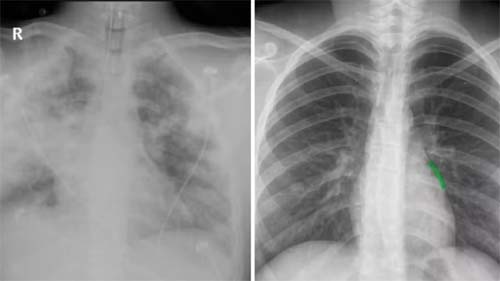

Lia comparou imagens dos pulmões do filho antes e depois da infecção, destacando a extensão da destruição causada pela bactéria. Segundo ela, “não foi o vapor que causou a morte do meu filho, mas seus pulmões foram danificados pelo uso do vapor”. A mãe também mencionou o hábito compulsivo de vaporização de Diego desde os 15 anos, apesar de seus esforços para impedi-lo. Diego também usou o dispositivo durante suas hospitalizações, apesar das advertências médicas de que poderia danificar seus pulmões.